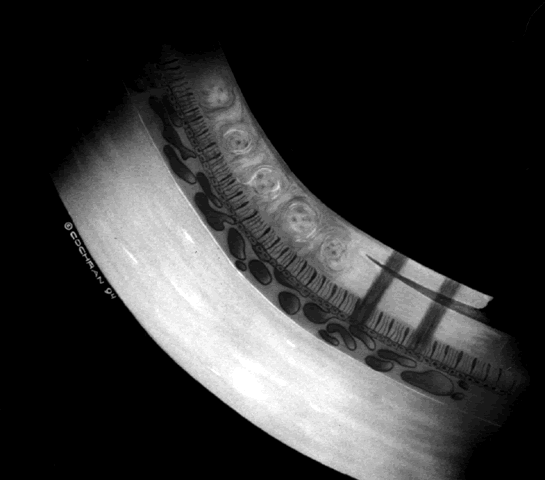

The suggested treatment is scleral buckling or vitreous surgery, including removal of the inner wall of the schisis cavity with extensive panretinal photocoagulation to protect against rhegmatogenous retinal detachment.36–38 The hallmark of this tractional detachment is visual field changes that are larger than expected relative to the schisis cavity.36 Previously, demarcation lines resulting from full-thickness retinal detachment have been reported posterior to the schisis cavity.39 Others have considered this finding to represent an undetected rhegmatogenous retinal detachment, but based on observations during surgery, we believe that this detachment can be reversible and is tractional in origin (Fig. 6).36

Fig. 6. Artist conception of a full-thickness traditional retinal detachment posterior to the schisis cavity before surgical intervention in congenital retinoschisis.

COATS' DISEASE

Coats' disease is an example of a vitreoretinal congenital vascular disease in which vitreous traction often plays a role leading to both preretinal and subretinal hemorrhage with resultant retinal detachment. Children with Coats' disease have been managed with vitreous surgery, scleral buckling, trans-scleral diathermy, cryotherapy, laser therapy alone, and laser therapy accompanied by injectable dyes (Fig. 7).40–42 Many different techniques have been employed because frequently neither the vessel abnormalities nor the vitreous traction can be resolved completely. With the possible advent of enzymatic surgery, such as use of plasmin or chondroitinase, it is hoped that a cleaner and more complete reduction of vitreoretinal traction will help advance the involution of these abnormal vessels without concurrent vitreous or subretinal hemorrhage.43

Fig. 7. Artist conception of resolution of a full-thickness retinal detachment after relief of vitreous traction by vitrectomy and inner-wall retinectomy in congenital retinoschisis.